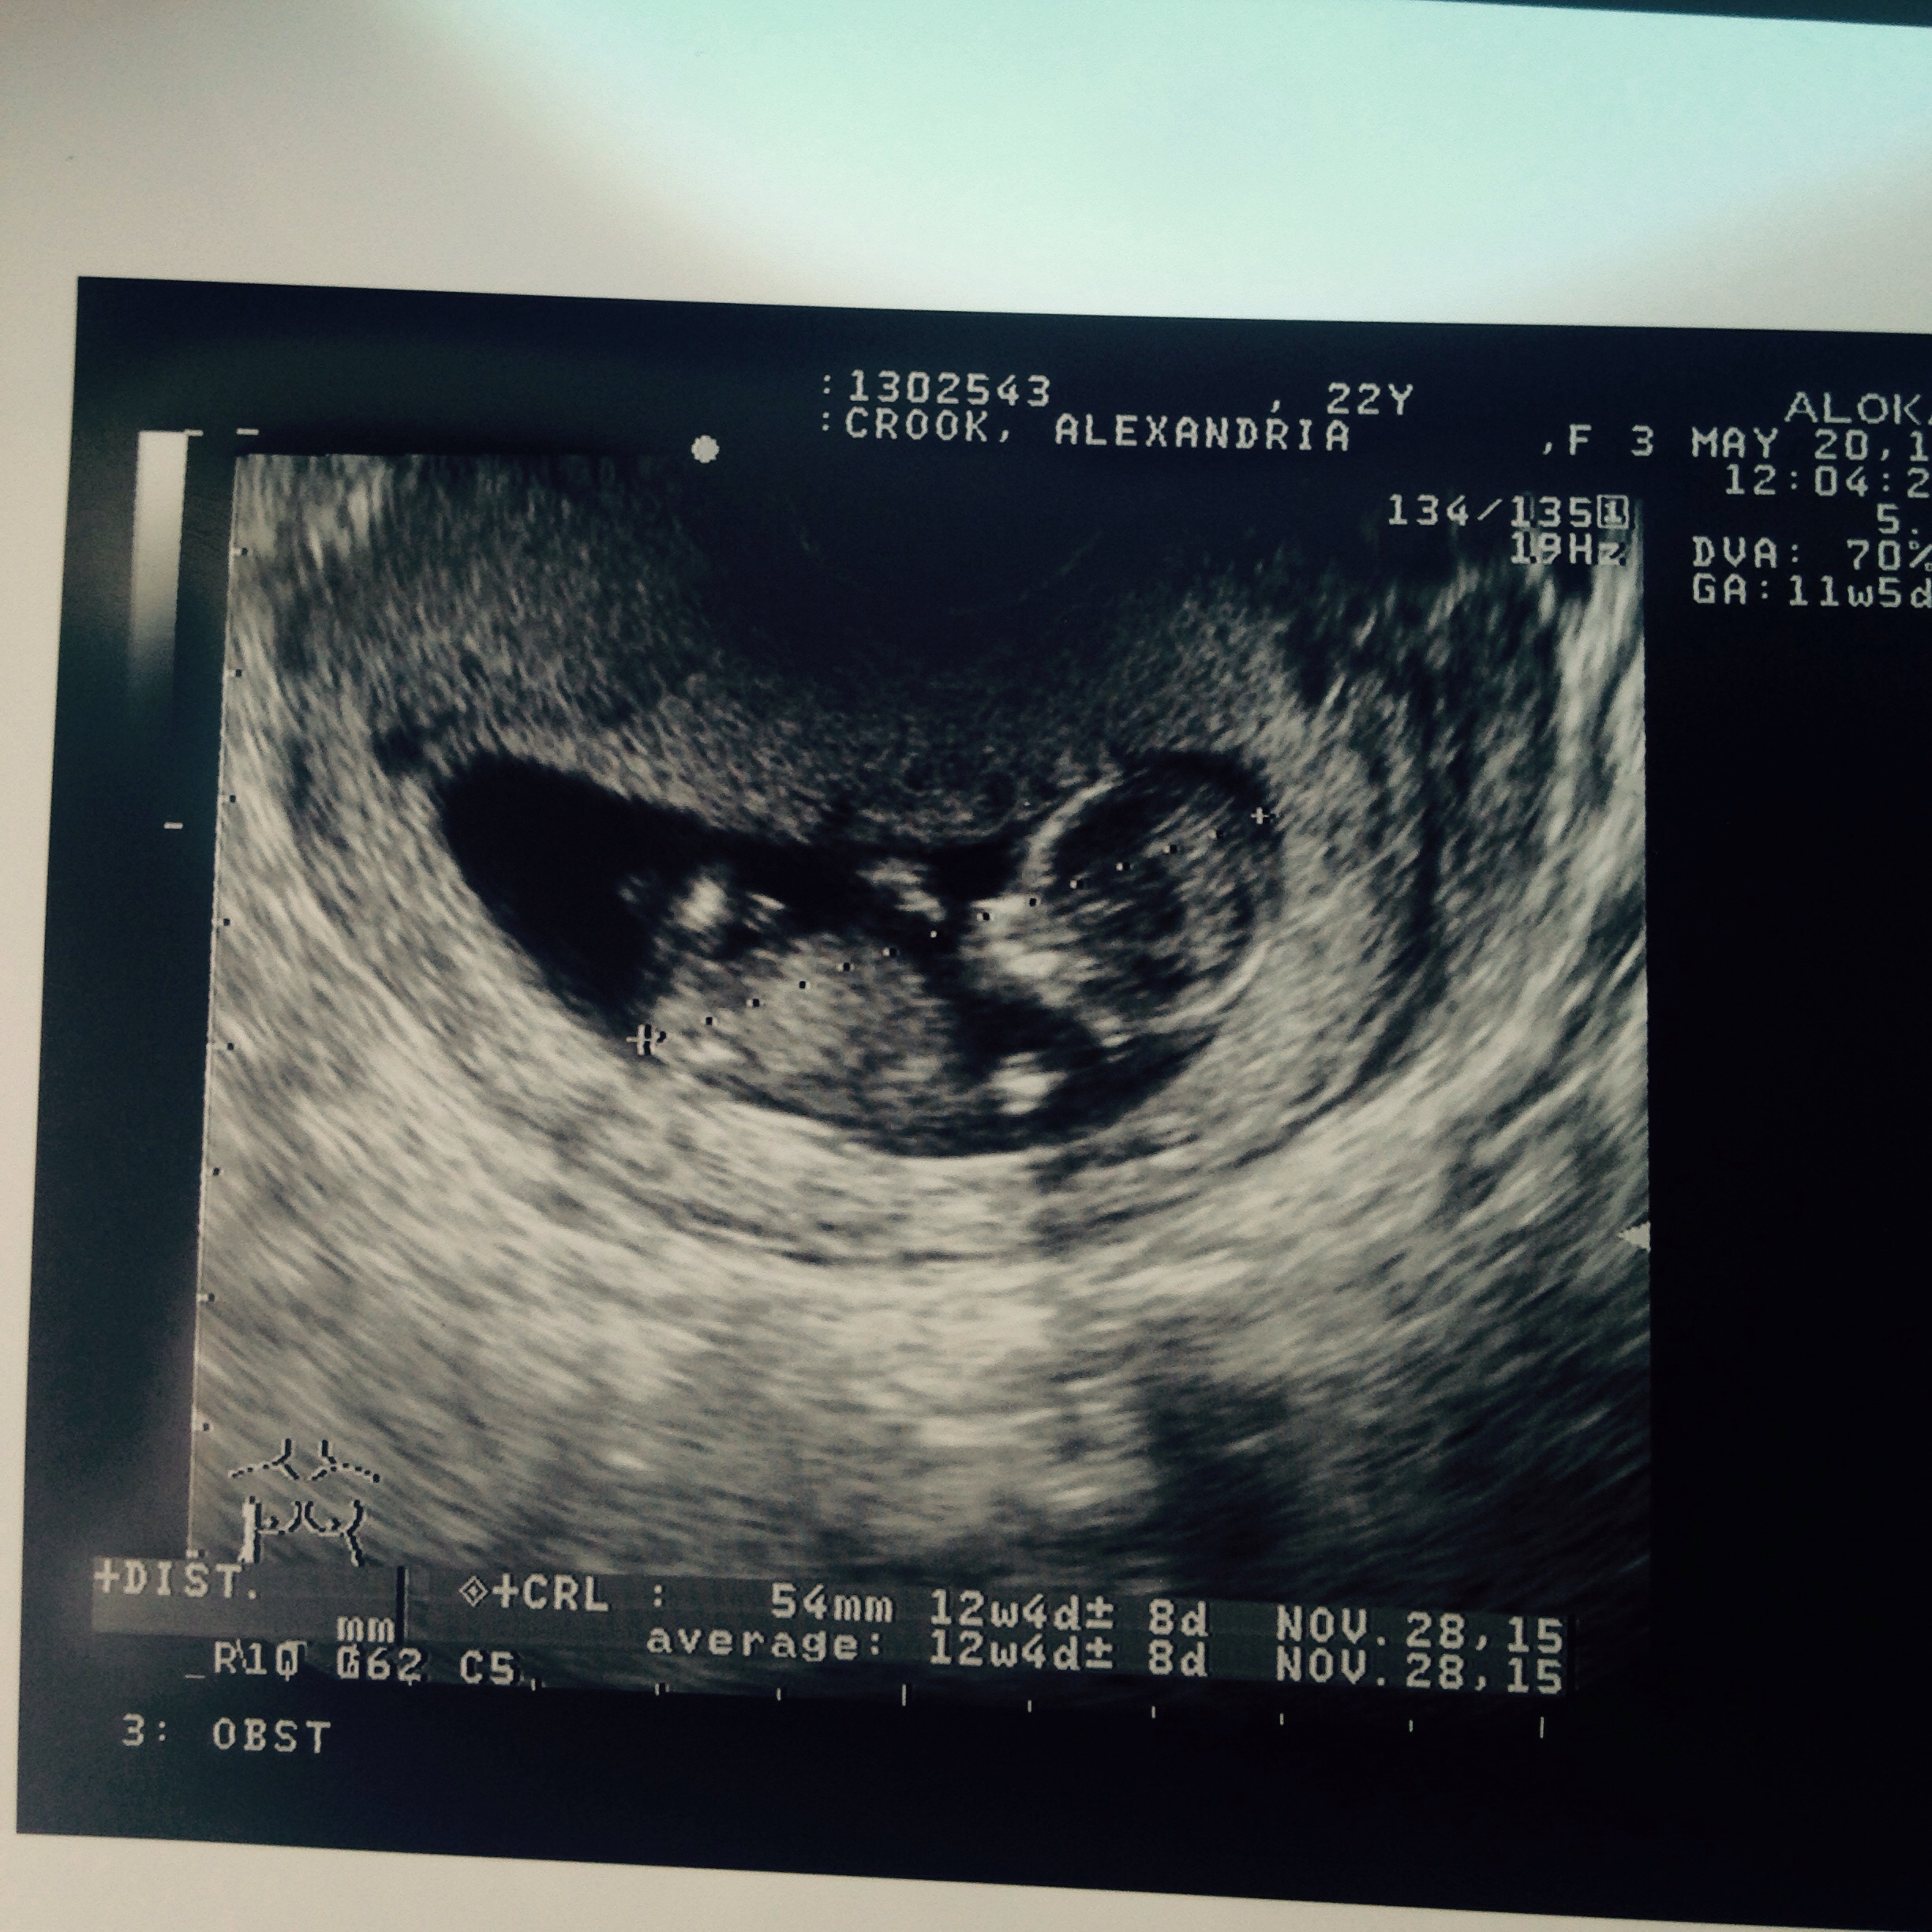

I had my first ultra sound today at 12 weeks

baby is healthy and oh so active!! Almost couldn't get a picture!! Lol